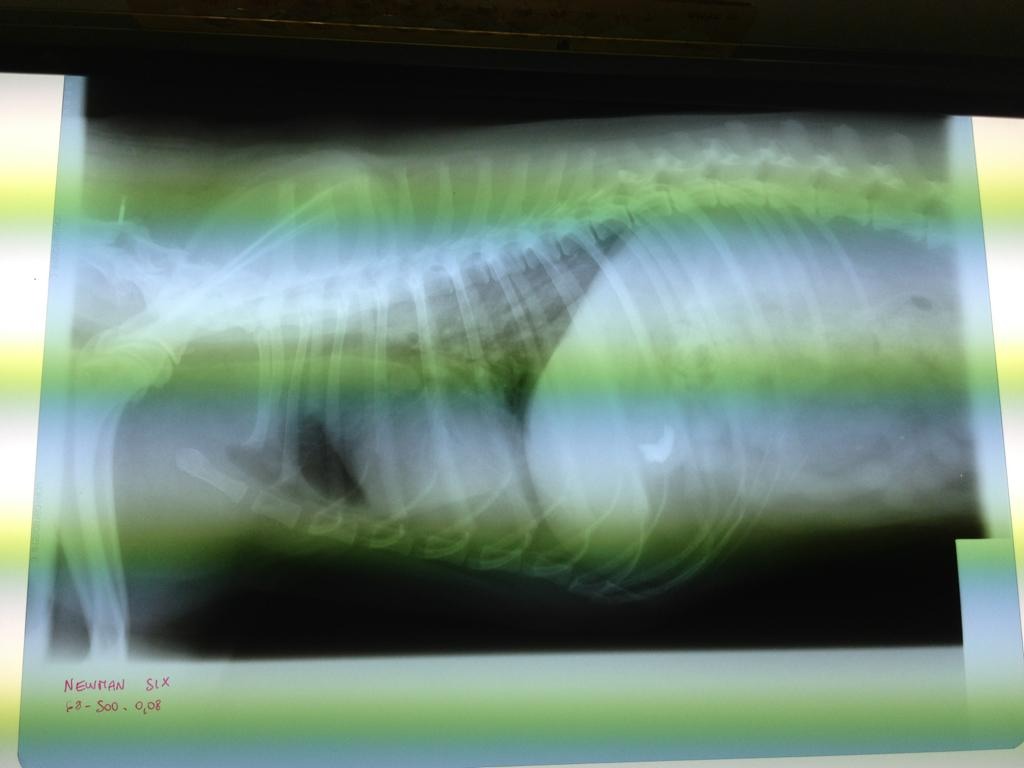

Ciao Mandy: dagli rx posso dirti al 99% che non è tumore...non li vedo...ed hai fatto stra bene a mandarmi le due proiezioni.

A questo punto però dovrei farti io alcune domande: 1) Difficoltà a respirare hai detto: fa fatica ad inspirare o ad espirare? 2) tossisce? 3) Hanno rilevato soffi cardiaci? Io, visto che dici essere peggiorato negli ultimi mesi, inserirei nella terapia (non vorrei però passare sopra i medici che lo stanno curando, quindi il mio è un consiglio nel massimo rispetto di colore sono li col cane, non potendolo io vedere) un diuretico. Il quadro polmonare mi sembra ascrivibile ad un edema polmonare. Quindi in tal caso darei Lasix o Diuren alla dose di 2 cpr ogni 12 ore. Questo lo darei anche senza avere le 3 risposte alle domande di cui sopra. Il profilo cardiaco mi sembra aumentato di dimensione..... Fammi sapere!!! I morti li portano via freddi.

Ho letto ora i tuoi commenti alle foto.....ero concentrato sulle radiografie.

Bene allora.....ma se ripeggiora, il diuretico lo darei lo stesso. Se l'animale mangia non ha effetti collaterali.... I morti li portano via freddi.

Non ti è arrivata la mail? Infatti mi sembrava strano che non mi avessi risposto. Te la incollo qui. 1. Entrambi 2. No 3. No Martedì sera gli hanno fatto una puntura di analgesico e una di un anti infiammatorio e con quelle è passato il peggio. Sembrava che stesse annegando. Siccome nella lastra si intravede un pezzo di osso nello stomaco pensano adesso che avesse avuto un gran dolore allo stomaco e respirava male per quello. Adesso sta bene il piccolo highlander. Aggiungo il diuren? |